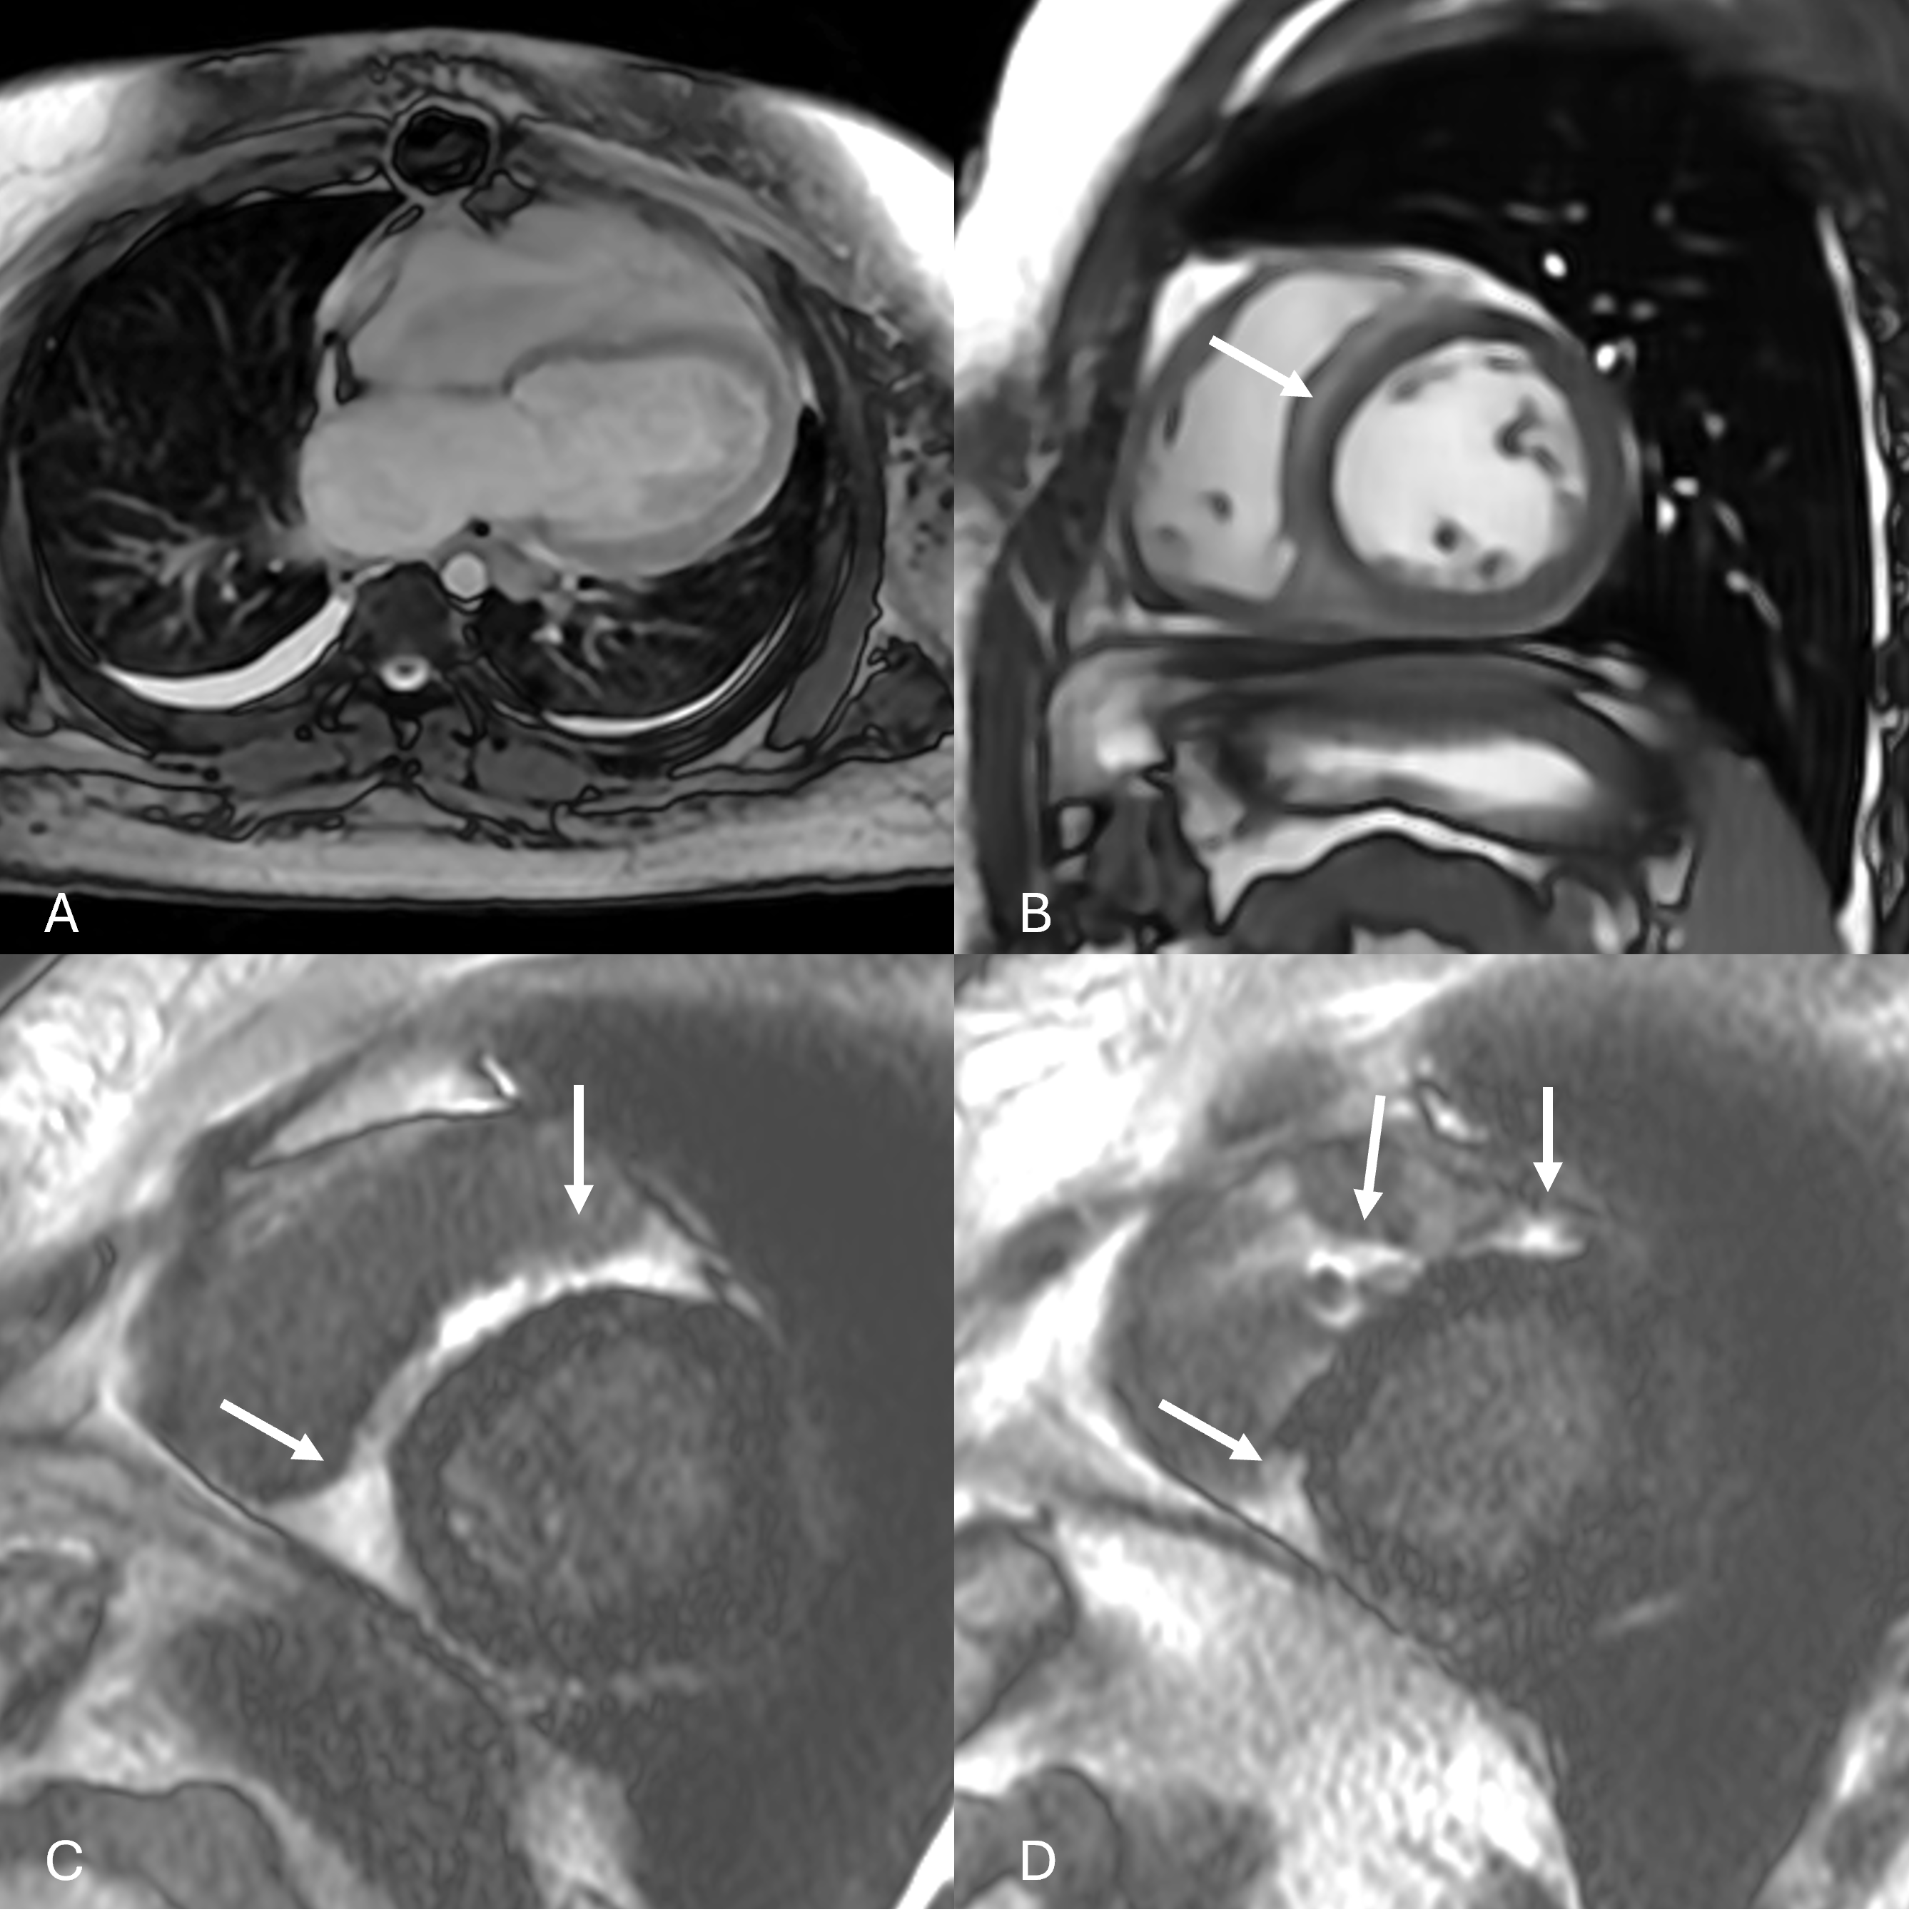

Figure 2: Panels demonstrating persistent and increased bilateral pleural effusions (A) and abnormal hypodense appearance of myocardium has increased along right ventricular aspect of intraventricular septum (B, arrow) on bSSFP imaging, and late gadolinium enhancement in the right ventricle has improved in the RV septum but may be appearing along the LV free wall subepicardium (C, D, arrows) on LGE imaging.